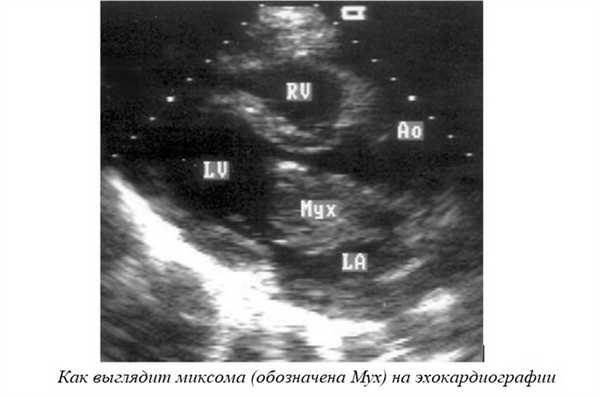

- (УЗИ сердца, Эхо-КГ) - главный способ диагностики миксом. На мониторе опухоль определяется как образование округлой формы с четкими краями, обычно находится в области межпредсердной или межжелудочковой перегородки в близости от створок клапанов. Миксома располагается на ножке, благодаря чему она может перемещаться из предсердия в желудочек и обратно. Иногда требуется проведение чреспищеводной эхокардиографии.

- Компьютерная или магнитно-резонансная томография (КТ, МРТ) - это дополнительные исследования. Их я назначаю при неясной УЗИ-картине, или чтобы лучше оценить объем разрастания опухоли.